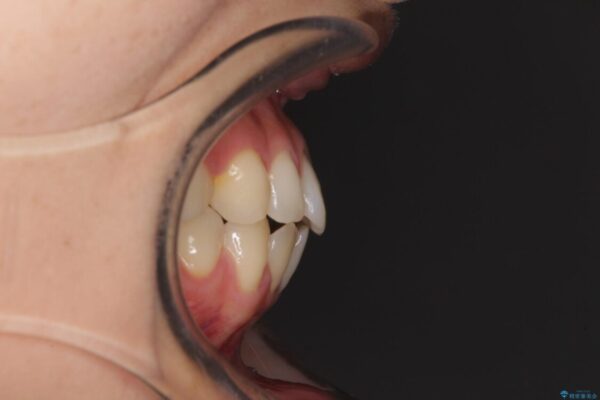

治療前

• 隙間だらけの歯列 インビザラインで改善 治療前画像